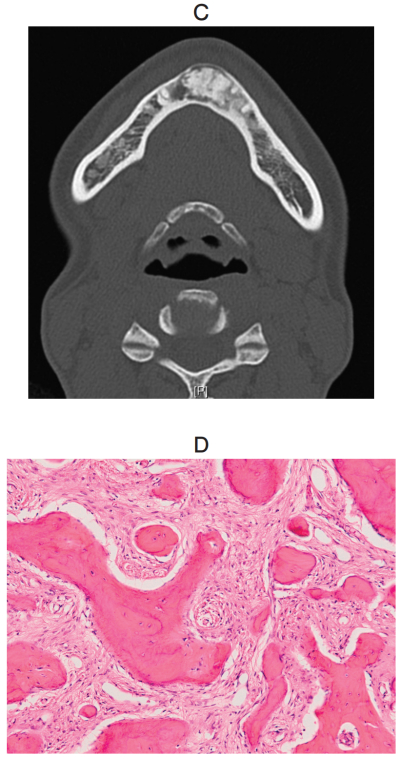

34歳の女性。下顎前歯部歯肉の膨隆を主訴として来院した。3か月前に気付いたが疼痛がないためそのままにしていた。膨隆は徐々に増大しているという。口腔内写真、エックス線写真、CT及び生検時のH-E染色病理組織像を別に示す。

診断名はどれか。1つ選べ。